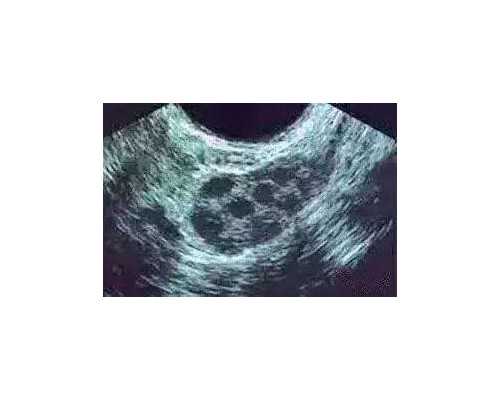

5、正常妊娠期间,血液中的雌二醇含量随怀孕周期而增高,双胎和多胎妊娠时升高更为明显。